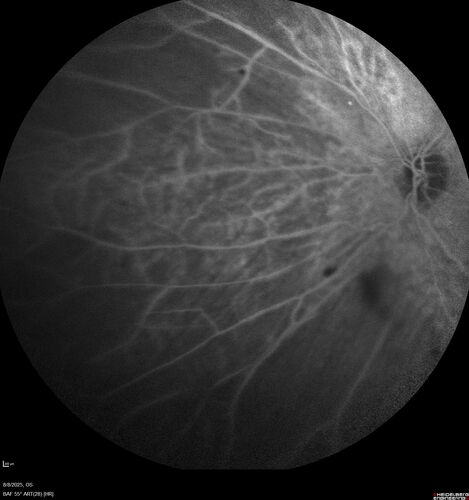

NPDR and Severe macular ischemia sudden vision loss

60 year old female with sudden vision loss OD 1 week ago. VA 20/63, 20/200. OCT-A and FA shows severe macular ischemia OU